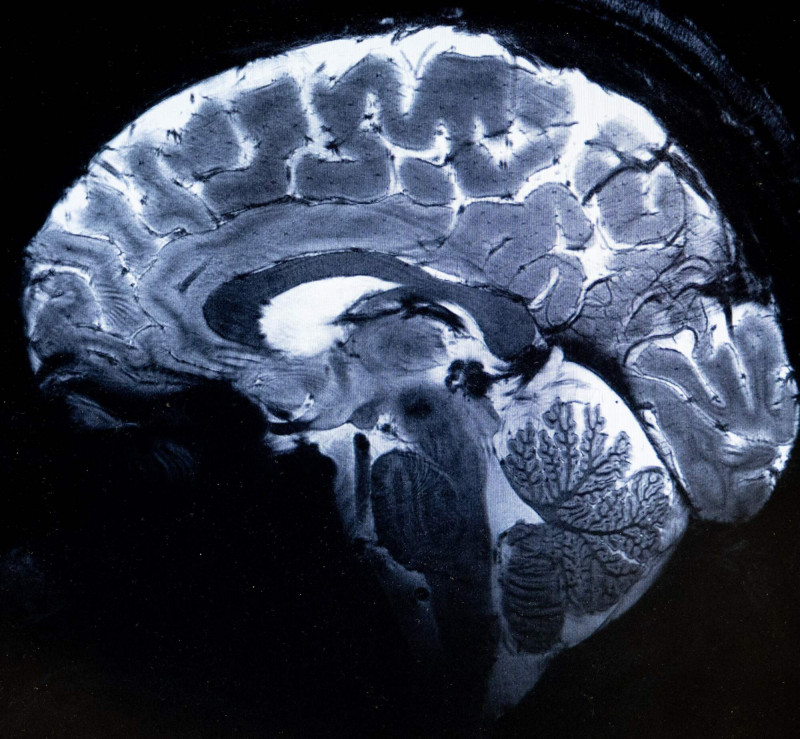

不單是情緒問題! 新研究顯示憂鬱症與「腦細胞」有關

1項對罕見死後腦組織的新研究顯示基因活動的變化,為理解憂鬱症的生物學基礎提供新視角。該研究發表在自然遺傳學期刊上,為針對特定類型腦細胞潛在治療鋪平道路,同時也促進對憂鬱症的科學認識。

根據每日科技(scitechdaily)報導,加拿大麥基爾(McGill)大學和道格拉斯(Douglas)研究所的研究人員發現,憂鬱症患者2種特定類型的腦細胞存在異常。

研究團隊分析了道格拉斯-貝爾(Douglas-Bell)加拿大腦組織樣本庫中的死後腦組織樣本。此樣本庫是全球罕見資源之一,包含來自精神疾病患者的捐贈樣本。

研究人員使用單細胞基因組學方法,分析數千個腦細胞的RNA和DNA,以確定哪些類型的細胞在憂鬱症中功能異常,以及哪些DNA序列可能導致這些變化。分析樣本包括59位憂鬱症患者和41位健康對照者的樣本。

研究結果顯示,參與情緒和壓力調節的1類興奮性神經元,和1種參與發炎反應的微膠質細胞(microglia)亞型(subtype),基因活性都發生改變。在這2種類型的腦細胞中,憂鬱症患者的許多基因功能均與健康對照組不同,表明這些關鍵腦系統可能存在功能失調。

麥基爾大學教授、道格拉斯研究所臨床研究員、研究通訊作者圖雷基(Gustavo Turecki)博士表示,研究反映出大腦中真實且可測量的變化,顯示憂鬱症不僅僅是情緒問題。

研究團隊下一步計畫研究這些特定類型腦細胞變化是如何影響大腦功能,以及是否可以透過針對這些變化來開發更有效的治療方法。